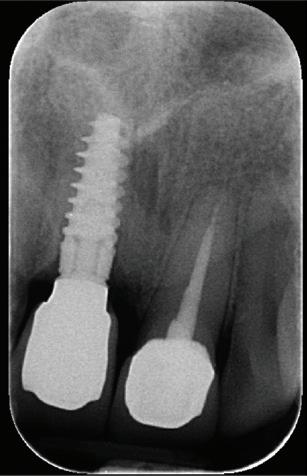

RECONFIGURAREA suportului osos implantar. În cazul prezentat, după ani de terapie ortodontică incorect executată, dezvoltarea dentară a pacientului a complicat obținerea unui zâmbet estetic. S-a reanalizat și s-a optat pentru abordare interdisciplinară care cuprinde chirurgia parodontală, un al doilea tratament

ortodontic și protetica pentru a oferi îngrijirea comprehensivă.

De asemenea, trebuie evaluate anual modificările radiografice. În ședința de inserție a restaurării, se înregistrează o radiografie bitewing standardizată pentru a permite evaluarea anuală a modificărilor osoase din jurul implantului. Remodelarea osului alveolar în primul an este bine documentată și depinde de tipul de implant utilizat; cu toate acestea, nu ar trebui să apară apical de primul filet al implantului. Prin urmare, este importantă abilitatea de a vizualiza filetele implantului pe radiografii. Modificările pierderii osoase de 2 mm sau mai mult după primul an reprezintă un semn de periimplantită. De îndată ce pierderea osoasă este recunoscută, pacientului trebuie să i se recomande terapia imediată pentru a opri procesul de boală.